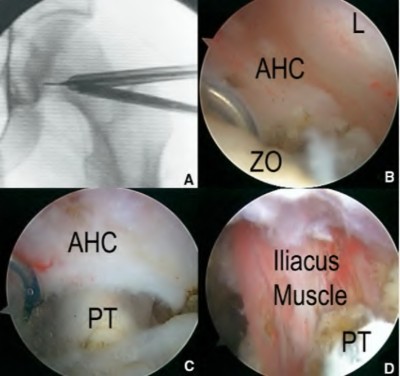

Question 93

Six months following an uncemented total hip arthroplasty, a patient complains of severe sharp groin pain when actively lifting their leg to get into a car. Radiographs reveal an acetabular component that is prominent anteriorly. Which of the following is the most likely diagnosis?

Explanation